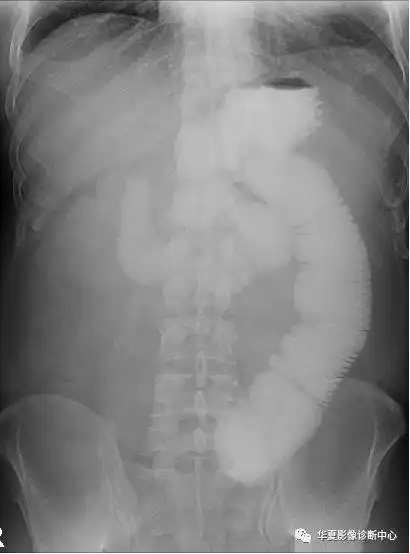

肠梗阻x线图片

一位典型肠梗阻患者的x线平片,可以看到明显的扩张积气肠管.

4,鱼肋征:空肠梗阻的重要x线征象.

典型的肠梗阻表现

肠梗阻x线表现